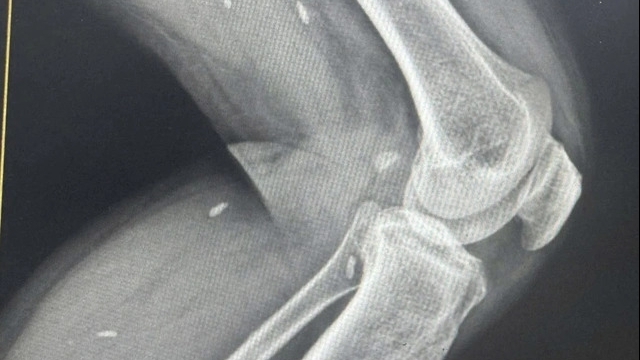

“Một lần họ tiêm 20 mũi ngay trên bụng mà tôi hỏi tiêm thuốc gì, có nguồn gốc xuất xứ gì không thì họ cũng không nói nên cảm thấy khá lo lắng(?)” - chị Vân cho hay.